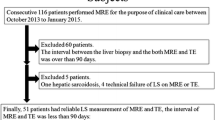

This prospective study was approved by our institutional review board. Informed consent in written was obtained from every subject prior to participation. Between May 2014 and January 2017, a total of 108 patients with chronic liver diseases were recruited consecutively for the study. All patients had undergone liver MRI (including MRE, IVIM-DWI) and TE. The inclusion criteria for patients with chronic liver diseases were as follows: no previous antiviral therapy; without a large amount of ascites; all subjects were confirmed by liver biopsy or liver resection; liver MRI and TE were performed within one month before liver biopsy or liver resection; acceptable image quality. Of these 108 patients, 6 were excluded from the study due to lack of histopathological results (n = 2) and poor images with artifacts (n = 4). In addition, 2 were excluded from the study on account of high iron content in liver. Finally, 100 patients (64 males and 36 females; mean age: 37.6 ± 9.3 years, age range: 22–58 years) were included in our study (Fig. 1, Table 1). Among the 100 patients, 81 were with hepatitis B, 8 with hepatitis C, 3 with non-alcoholic fatty liver disease, 2 with drug-induced hepatitis, and 6 with autoimmune hepatitis (Table 1).

Flowchart of the study enrolment population. The 25 healthy volunteers without ultrasound-guided liver biopsy and with no history or of evidence alcohol abuse, chronic liver disease, focal liver lesions, or liver dysfunction were assumed to have fibrosis stage F0 and inflammatory activity grade A0 in this study. *F0/A0 group includes 1 patient with pathologically proved F0/A0 and 25 volunteers who were regarded to have healthy livers

In the meantime, 25 healthy volunteers (7 males and 18 females, mean age: 31.5 ± 12.9 years, age range: 21–69 years) were recruited consecutively for the study (Fig. 1, Table 1). All the healthy subjects with no ultrasound-guided liver biopsy had undergone MRE, IVIM-DWI, and TE. The inclusion criteria for the healthy volunteers were no history of alcohol abuse; without chronic liver disease or focal liver lesions; without abnormal liver function test results; and acceptable image quality.

Fibrosis staging and inflammatory activity grading

Histological quantification of HF was performed in 94 patients by liver biopsy and 6 patients by surgical hepatic resection. The 25 volunteers with healthy livers were regarded to have fibrosis stage 0 and inflammatory activity grade 0. Finally, the fibrosis stage distribution is as follows: F0, n = 26; F1, n = 17; F2, n = 33; F3, n = 25; and F4, n = 24. The inflammatory activity grade distribution is as follows: A0, n = 26; A1, n = 20; A2, n = 56; and A3, n = 23 (Fig. 1, Table 1).